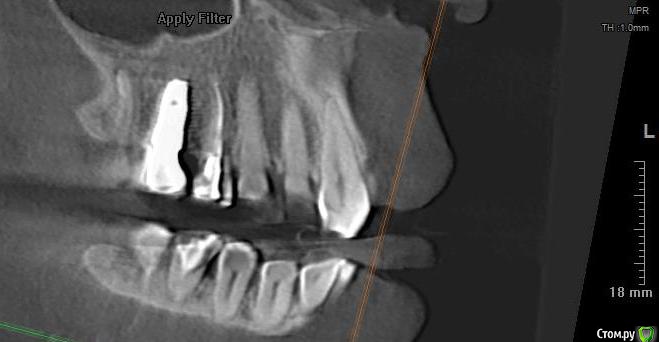

В феврале 2018 была проведена одномоментная имплантация системой Dentium верхней правой пятерки,  имплантат хорошо прижился, в сентябре протезирование винтовой металлокерамической коронкой. Коронка изначально была не идеальна, не были учтены мои пожелания пока ходила с временной, некоторые моменты пришлось корректировать уже во рту после установки. С самого начала я ее чувствовала как инородный предмет (2 импланта, которые стоят с 2008 года, я не чувствую вообще), но решили пока походить так, чтобы привыкнуть.

В ноябре 2018  поставили диагноз артроз и назначили хондопротекторы+гиалуроновая кислота+коллаген для восстановления хряща. Примерно через восемь месяцев приема препаратов на всей верхней и нижней челюсти появились наросты (экзостоз). Челюстно-лицевой хирург сказал, что удалять пока смысла нет, наросты дискомфорта не причиняют, визуально не видны и лучше не лезть (осень 2019) . Я обратилась к тому же врачу-стоматологу с жалобой на дискомфорт в области имплантата.  Чувство  инородного предмета во рту усилилось, ощущение онемевшего "замороженного" зуба даже при чистке щеткой.  На снимке доктор  проблем с имплантатом  не обнаружил. Решили снять и подкорректировать коронку, в результате при вскрытии пломбы повредили головку винта, открутить не смогли. Промучились час, запломбировали обратно и отпустили. Как вариант доктор предложил срезать коронку, но я не решилась на такие радикальные действия. С марта 2020 года появились ноющие боли в верхней правой половине челюсти и головные боли, отдающие в правую часть лба. Я грешила на имплантат, десна вокруг коронки была розовая, но болезненная с внешней и внутренней стороны. Поехала к тому же врачу, сделали снимок, с имплантатом  все хорошо, но доктор сказал, что воспалилась соседняя четверка (стояла большая пломба), хотя на надкусывания и постукивания зуб не реагировал.  Вскрыли пломбу, зуб пролечили, каналы запломбировали (июнь 2020), головные боли ушли. Четверку подготовили к покрытию коронкой.

На сегодняшний день  имеется следующее: постоянные тянущие ощущения в области 4-го зуба и имплантата, легкое реагирование на горячее/холодное, болезненная десна вокруг коронки. Доктор настаивает на покрытии 4 зуба коронкой, говорит, что реакция на горячее/холодное пройдет.

post-3819-0-90305200-1595925032_thumb.jpg

post-3819-0-99302800-1595925046_thumb.jpg

ссылка на КТ (Пикассо)